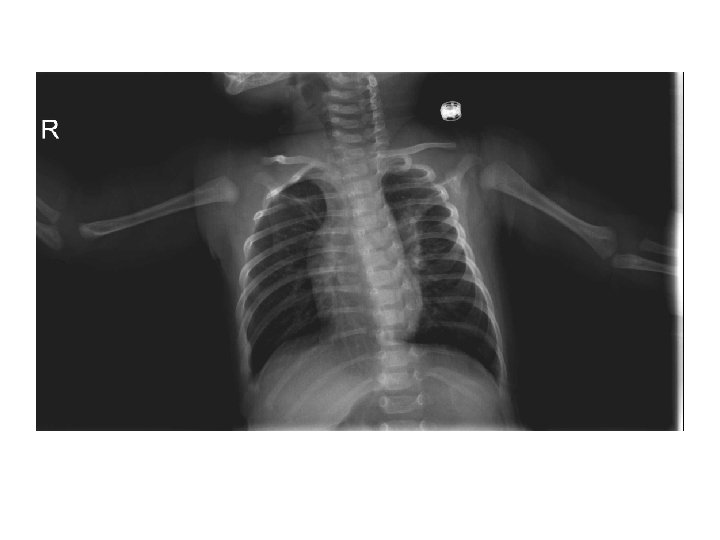

Radyoloji ü Krup klinik tanıdır ü PAAC ü Boyun grafileri

Steeple sign